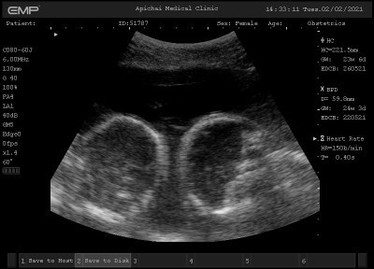

อยากให้แม่ๆช่วยตั้งชื่อจริงให้ลูกๆหน่อย บ้านนี้ใกล้คลอดแล้วยังคิดไม่ออกเลย แฝดชาย-หญิง